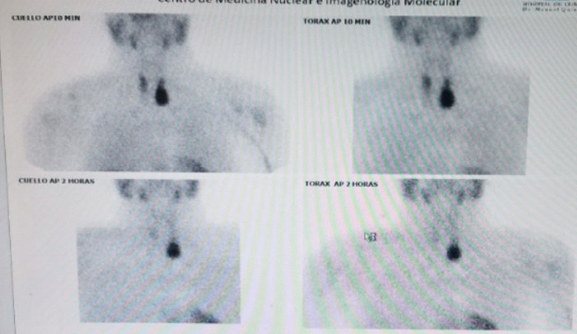

Parathyroid scintigraphy with Technetium 99 sestamibi and SPECT: Hypercaptured left lower parathyroid tissue (Figure 2).

Figure 2 Persistence of radiolabel at the level of the left inferior parathyroid gland is observed with the passing of time of evaluation.